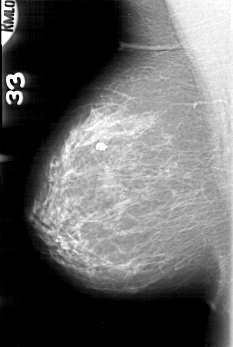

D_4089_1.RIGHT_CC

RIGHT_CC LINES 5206 PIXELS_PER_LINE 3346 BITS_PER_PIXEL 12 RESOLUTION 43.5 NON_OVERLAY